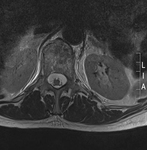

IRM de la columna lumbar: vista transversal (secuencia ponderada en T2) con fractura osteoporótica del cuerpo vertebral T12

De la colección personal del Dr. B. Nurboja y D. Choi

Ver esta imagen en el contexto de la/s siguiente/s sección/es:

Traumatismo de la columna toracolumbar